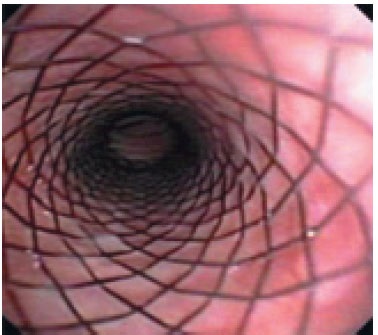

Endoszkópia a legjobb diagnosztikai értékeléséhez a légcső és a hörgők, de végrehajtására csak érzéstelenítéssel. Bronchoszkópia lehetővé teszi, hogy belsejében a légcső az egész hosszában, hogy értékelje az állam az nyálkahártya, hogy értékelje a mozgás a légcső során légzési ciklust. Tracheoscopy „arany standard” diagnózis és használják megerősíteni a diagnózist. A jelenléte a változások a lumen a légcső és a hörgők 4 fok trachea összeomlása. A légcsövet a „normális” van egy csaknem kör alakú annak teljes hossza mentén. Az egészséges állatok légcső áll sobraznyh alakú porcos gyűrűk egymáshoz háti légcső membrán. Dorsalis tracheális membrán általában tekinteni, mint a hosszanti simaizom rossz szakaszok során lélegzik. A légcsövet borított nyálkahártya, amelyeket át nézve a porcos gyűrűk. Nyálkahártya „OK” úgy néz ki, sima, halvány rózsaszín, nyálkahártya alatti réteg gazdag áthatja kapillárisok (3. ábra). Ha a szint 1 tracheális összeomlása is megfigyelhető, hogy az alak a légcső alig változott, dorzális membrán enyhén laza, a porc gyűrűk alátámasztó normális formában légcső, a légcső lumen csökken mintegy 25% (4. ábra). Amikor a 2. fokú összeomlás dorzális membrán kifeszített és laza, kissé lapított porcos gyűrűk, tracheális lumen 50% -kal csökken (5. ábra). Összecsukása 3. fokozatú azzal jellemezve, hogy a dorzális membrán laza úgy, hogy szinte érinti a dorzális a porc gyűrűk porcos gyűrűk dorsoventrally lapított, tracheális lumen csökken 75% (6. ábra). 4. fokú összeomlása a légcső: dorzális membrán fekszik a porcos gyűrűk légcsőgyűrűket lapított és telepített gyakorlatilag nem légcső lumen (7. ábra) (a Tangner CH, Hobson HP: Egy retrospektív vizsgálatban 20 kezelt esetek összeesett légcső / Vet Surg 11: 146, 1982).

Endoluminális helyreállítása légcső keresztül önmagától táguló stent készült Nitinol (nikkel-titán ötvözet) használt a közelmúltban. Ez protézis eredetileg tervezett bővítése sérült artériák és epeutak emberekben. Az általunk használt biliáris stentek Nitinella, amelyeknek számos előnye van: atraumatikus végei csökkentse annak lehetőségét, traumás légcső fal, nagy szilárdságú ellenállás, jó kapacitás bővítését, könnyen implantáció, radiopak markerek mindkét végén a sztent (ris.11,12).

A telepítés után a stent a légcső ürege, a stent fokozatosan alkalmazkodik az üreg méretét a légcső. Az előnye ennek az eljárásnak, mint a műtéti stabilizálásra ¬sostoyat az, hogy nem invazív, és mindössze 5-10 perc, függően a gyakorlati képesség (ris.14,15).